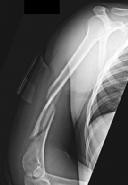

Question 11:

A 4-month-old infant is being treated with a Pavlik harness for Developmental Dysplasia of the Hip (DDH). At the two-week follow-up, the mother notes that the baby is not kicking or extending the knee on the treated side, though ankle and toe movements are intact. Which of the following is the most likely cause of this finding?

Options:

- Avascular necrosis of the femoral head due to excessive abduction

- Femoral nerve palsy due to hyperflexion of the hip

- Obturator nerve palsy due to excessive abduction

- Sciatic nerve compression from the posterior harness straps

- Slipped capital femoral epiphysis caused by the harness

Correct Answer: Femoral nerve palsy due to hyperflexion of the hip

Explanation:

Femoral nerve palsy is a known complication of Pavlik harness treatment. It is typically caused by excessive hyperflexion of the hip in the anterior straps. It presents clinically as an inability to extend the knee (quadriceps weakness) or a lack of kicking on the affected side. The treatment is to temporarily loosen the anterior straps or remove the harness until nerve function returns.